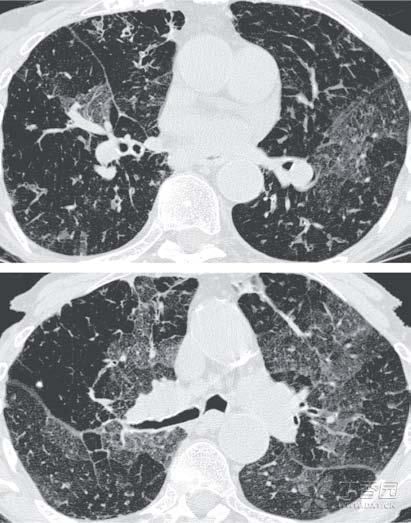

在研究到免疫基因的时候,原本抱着“*子烟电**无害”想法的研究人员们发现了一个他们怎么也没想到的问题,他们发现,来自*子烟电**民人群的实验者,他们的免疫基因几乎“全军覆没”,

全部被一种“神秘物质”抑制!

只见实验报告中写道:

普通烟民有 53 种免疫基因受到了抑制,*子烟电**民除了这 53 种免疫基因受到抑制之外,额外还有 305 个免疫基因受到抑制(总共 358 个)。

这也就表示,在抑制人体免疫基因数量这一点上,

*子烟电**的危害是香烟的7倍!

在后续的研究中,*子烟电**烟雾气溶胶会引起血小板聚集增加,可能导致血管出现微血栓,说明*子烟电**在增加心血管系统风险并引发心脏病发作方面,

与传统香烟并无异处!

随后,研究人员还发现,电池加热烟液产生的气溶胶中,含有对心血管有害的醛,包括甲醛、乙醛和丙烯醛等,而如今,人们却通过*子烟电**,

将甲醛吸入了自己的身体!

闭塞性支气管炎。

闭塞性支气管炎是一种罕见、致命且不可逆的阻塞性肺病,若患上了这种疾病,别说抽烟了,可能很长一段时间都要在抽血中度过了。

研究人员还发现,这些甜甜的“烟雾”除了会引起这种罕见的肺病之外,

还对DNA构成有潜在危害!

FDA联合康州大学(University of Connecticut)的化学家们发现,这种含有双乙酰的化合烟雾会在人体中作用,

导致DNA结构发生突变!